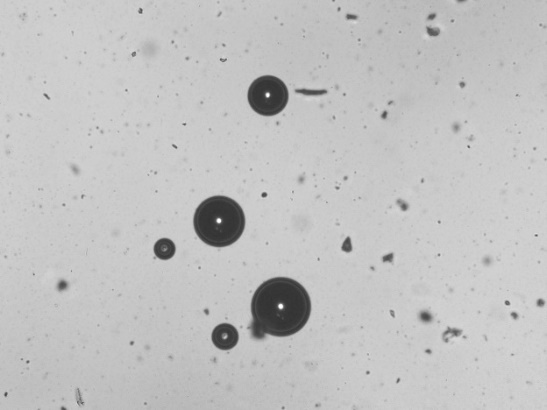

Dark field microscopy

The formed liposomes were seen under Magnus INV manufactured by Olympus Optosystems at magnifications of 10X and 40X with inverse phases for better viewing.

Fig. 8: Image of liposome under darkfield microscope 40X and 10X, respectively

Images under dark field microscope

Optimized batch B3 under a dark field microscope had been viewed in inversed phase to view the interior of the liposomes in 40X and 10X, respectively. Instrument used Magnus INVS (220-240V-0.3A, 50-60Hz). The liposomes were regular and spherical.